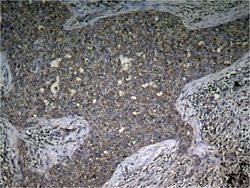

ARG51712 IHC

Full details

Method:

Other validation